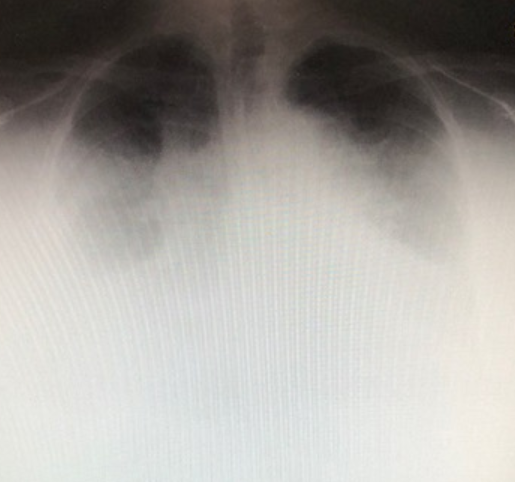

症例提示:70歳台女性

入院前経過:以前より高血圧があったが医療機関を受診せず。1~2か月前より全身のむくみがあり、時々呼吸が苦しくなった。2~3日前より呼吸苦が増悪し、救急車にて当院に搬送。到着時は仰臥位になれない「起坐呼吸」の状態。

入院時胸部単純X線像

心拡大、胸水貯留、全身浮腫が著明